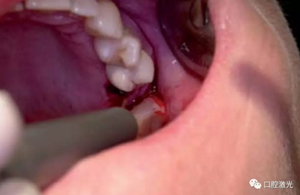

拔牙后,將光纖探至牙槽窩底部,通過低功率激光(小于100mW)進行刺激,促進出血。當血液充滿牙槽窩后,設置激光為凝血預設方案(4~6W)。將光纖端面距離血液表面1至2mm,散焦模式照射30至45秒,促進其凝固即可。該操作雖然需要適當?shù)木毩暫筮_到熟練的狀態(tài),但總體而言仍然是十分簡單、快速的。隨后,患者應減少對該區(qū)域進行刷牙或漱口。術(shù)后3天和4周的復診可以看到不同案例下都取得了很好的恢復效果,牙槽嵴均得到了很好的保存。

激光輔助治療術(shù)中